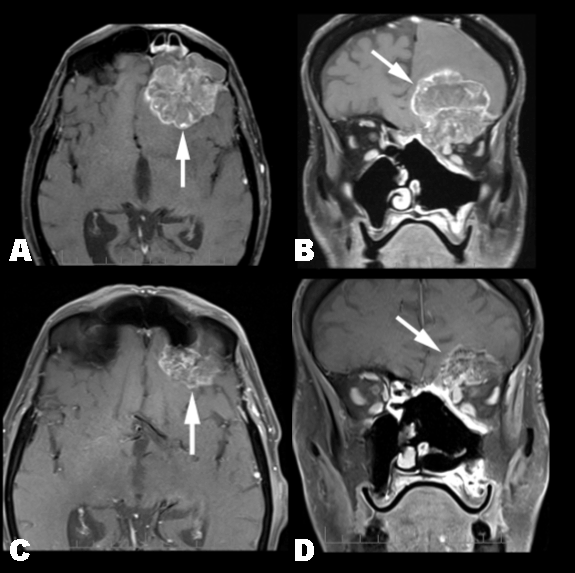

Interim MRIs during treatment showed progressive shrinkage of the primary tumor, reduced mass effect in the left frontal lobe, and resolution of the midline shift and ventricular compression. After 11 cycles of FOLFOX chemotherapy, the primary lesion measured 22.8x17.3x23.3 mm consistent with a partial response by RECIST criteria (Figure 1). Moreover, the majority of the T2 bright tumoral signal resolved suggesting fibrosis. Finally, tumor was no longer detected in the frontal sinus and superior orbital fissure, and there was significant intranasal and left globe tumor regression.

Figure 1: Pre- and post-treatment T1 post-contrast MRI images showing partial regresion of tumor. (A, C – Axial image B, D – coronal images).